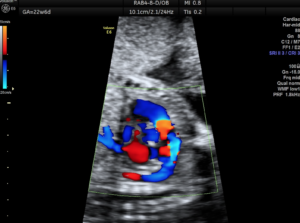

Ο έλεγχος της εμβρυϊκής καρδιάς στο δεύτερο τρίμηνο είναι πια πλήρης δηλαδή ελέγχεται τόσο η ανατομία όσο και η λειτουργία και η ανάπτυξη της εμβρυϊκής καρδιάς. Είναι εφικτό να διαγνωσθούν σχεδόν όλες οι μείζονες και οι ελάσσονες συγγενείς καρδιοπάθειες. Κατά τον προγεννητικό έλεγχο δεν δύναται να διαγνωσθούν κάποιες μυοκαρδιοπάθειες, οι καναλοπάθειες, οι ανωμαλίες των στεφανιαίων αγγείων, το μεσοκολπικό έλλειμμα, η παραμονή του βοταλλείου πόρου, οι υποβαλβιδικές στενώσεις και η μερική ανώμαλη επαναφορά των πνευμονικών φλεβών.

Η εξέταση πρέπει να γίνεται από παιδοκαρδιολόγο εξειδικευμένο στην εμβρυϊκή καρδιολογία.